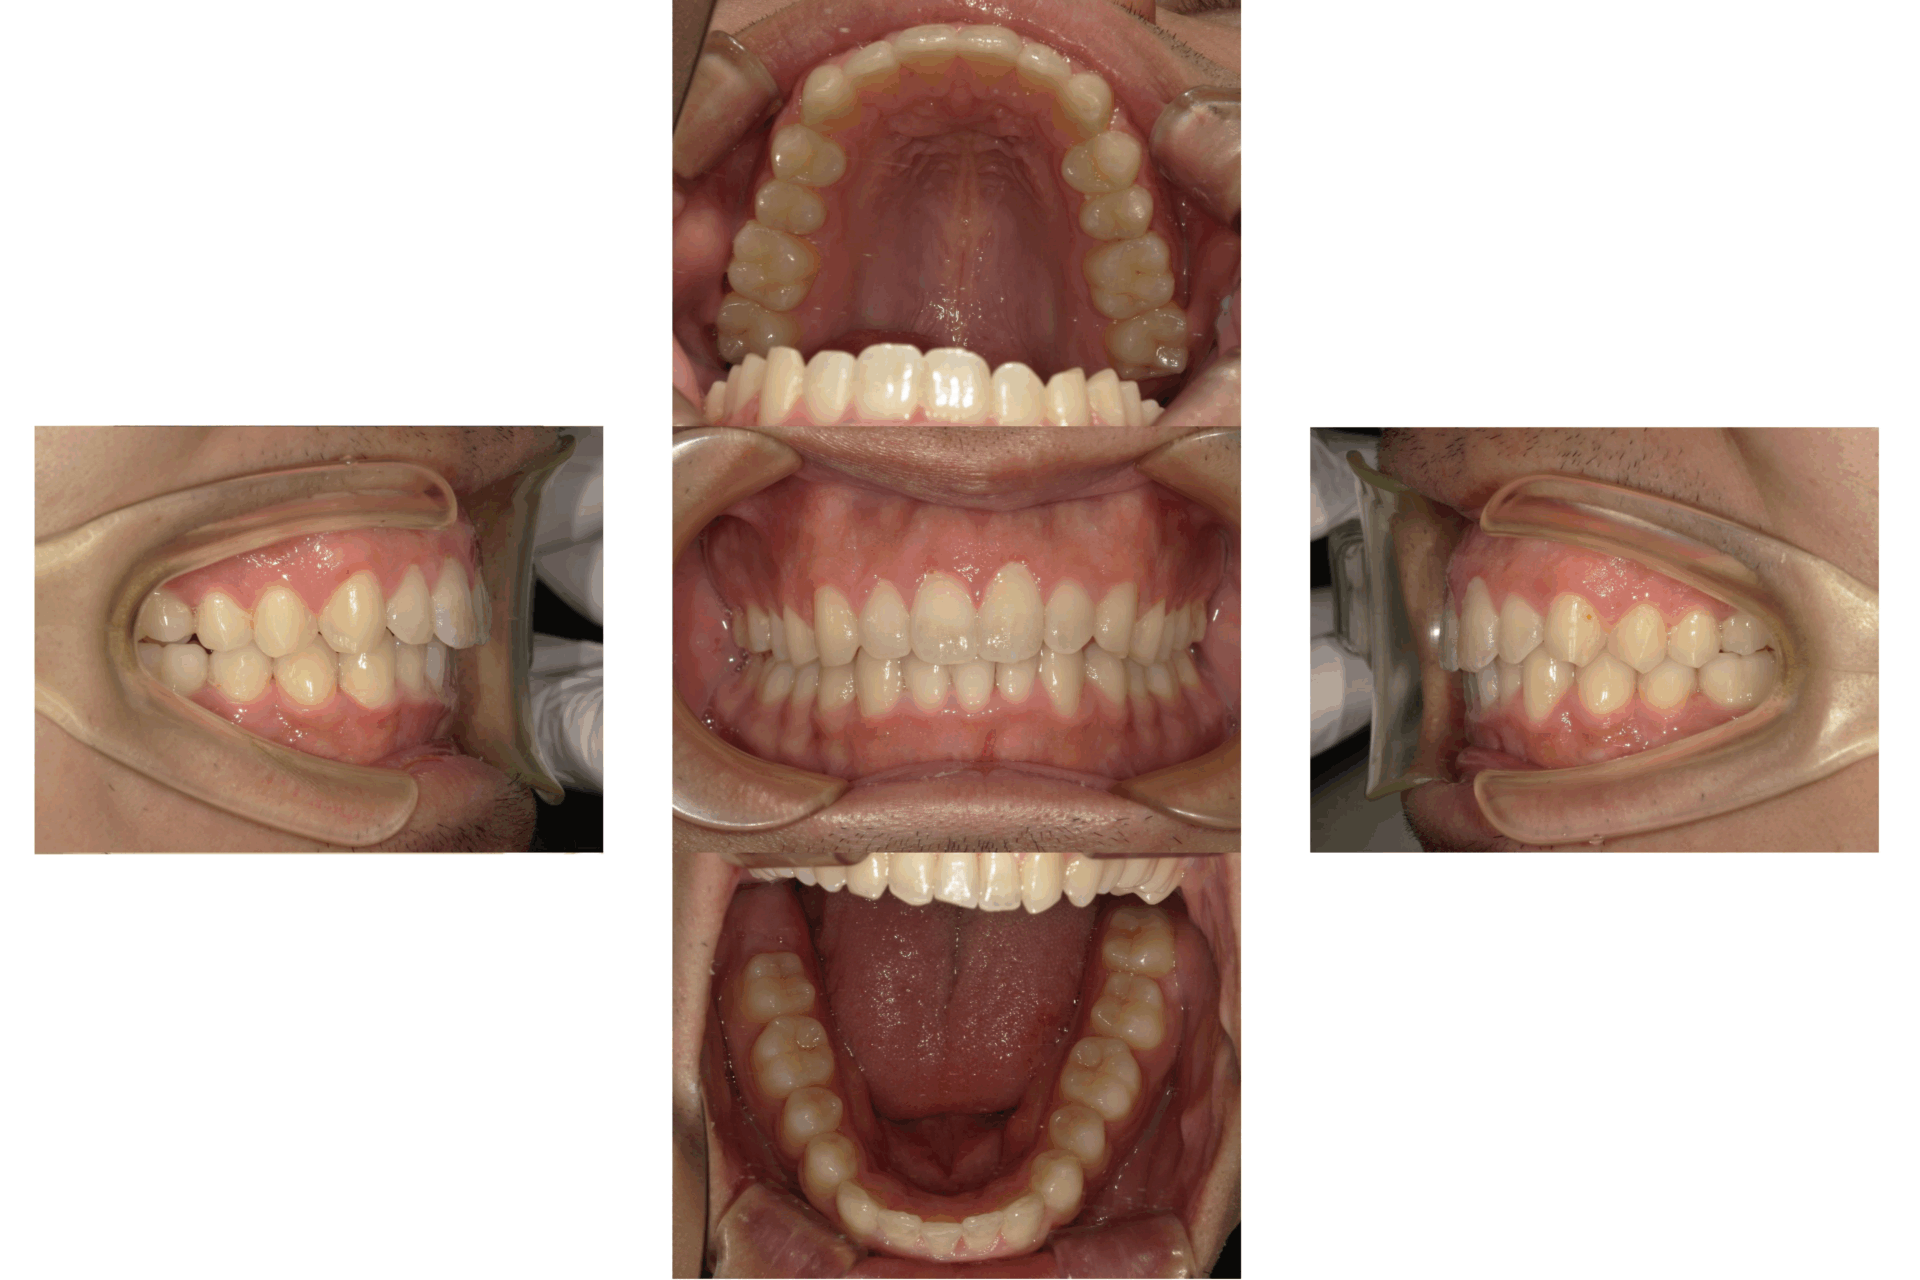

20代、男性、ワイヤー

| 施術内容 | 主訴:でこぼこで食べ物がよく挟まる。虫歯や歯肉炎に悩まされてきた。 詳細:ワイヤー矯正での歯並び改善 とても磨きやすくなったと満足されてます。 |

| 治療期間 | 16ヶ月(2/3現在 治療終了) |

| リスク・副作用 | ■リスク・副作用 ・治療の初期段階では、痛みや不快感が生じやすくなりますが、一週間前後で慣れます。 ・歯の動き方には個人差があるため、予想された治療期間より延長する場合があります。 |

| 費用 | ワイヤー矯正 60万円(税込660,000円) |